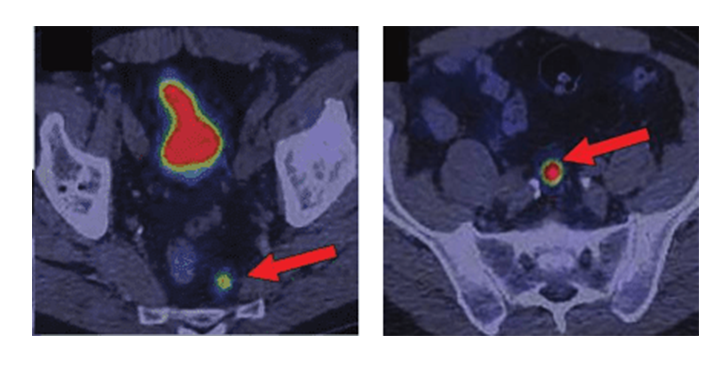

Для установления наиболее эффективного радиофармпрепарата в каждом конкретном клиническом случае необходимо воспользоваться нижеприведённой таблицей. Производится это путём сопоставления двух параметров, полученных из иммуногистохимического: Grade (G) и Ki-67 (параметры агрессивности опухоли).

РФП |

Grade 1 Ki-67 ˂2% |

Grade 2 Ki-67 3-10% |

Grade 2 Ki-67 11-19% |

Grade 3 Ki-67 ˃20% |

68Ga-DOTA-TATE и 68Ga-DOTA-NOC |

++ |

++ |

++ |

- |

18F-ФДГ |

- |

- |

+ |

++ |

++: чувствительность метода высокая;

-: чувствительность метода низкая;

+: чувствительность метода одинаковая (ПЭТ/КТ можно выполнить как с 68Ga-DOTA-TATE и 68Ga-DOTA-NOC, так и с 18F-ФДГ).